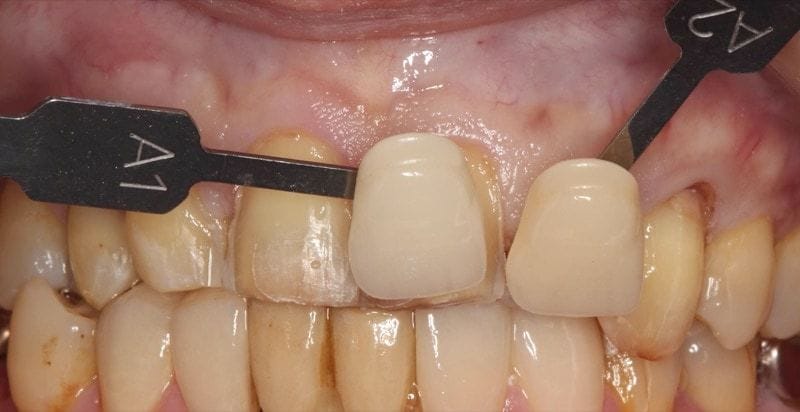

圖示:術中比色,數位化掃描製作流程讓成品更接近真牙

實際療程中,我們處理了原來牙齒內的齲齒問題(左上犬齒),此外我們可以看到,全瓷貼片的牙齒修磨非常保守,能夠保留大部分的齒質,幾乎維持整顆牙齒的完整性。

利用比色板放在牙齒旁邊拍照紀錄,我們就能夠提供牙技師需要的顏色資訊,讓成品更能夠擬真自然。經過數位化口內掃描及咬合記錄,牙技師端也採用CAD/CAD的數位流程產出修復體。